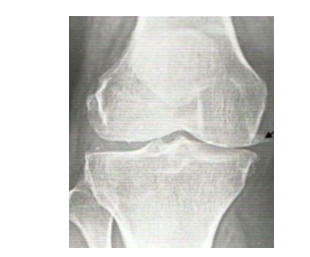

Would you like your knees to go from this: